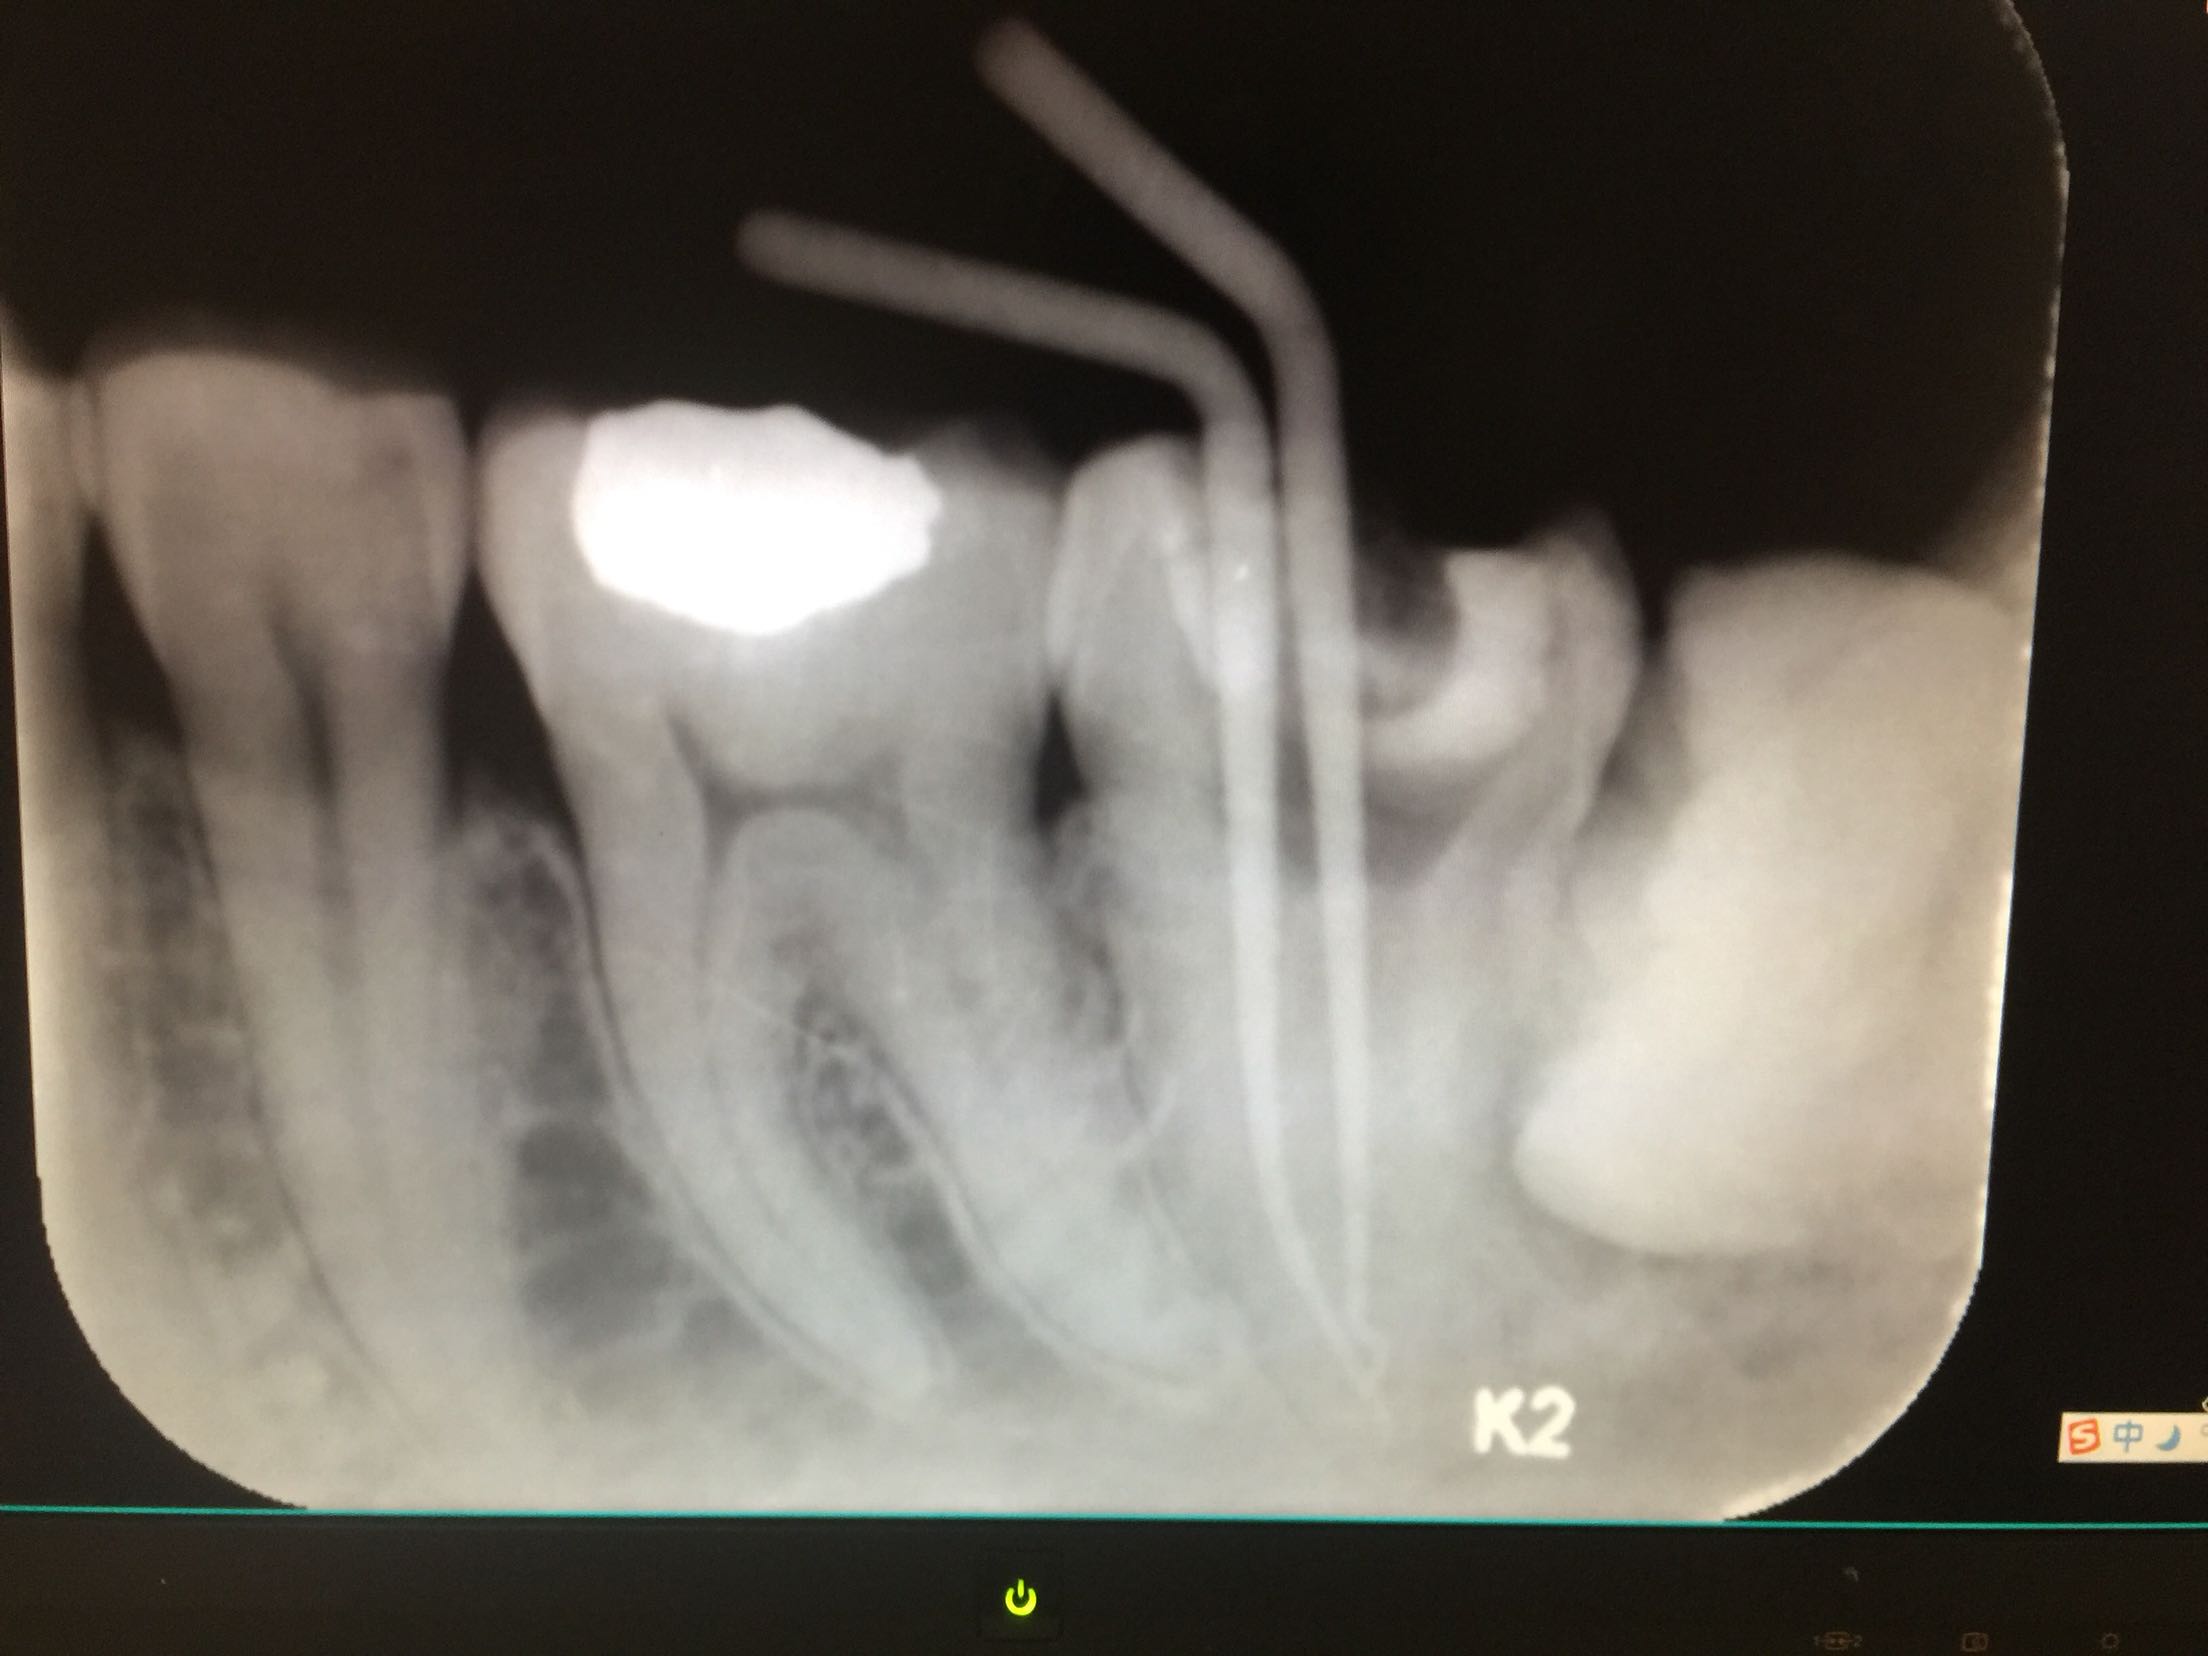

检查:37牙合面可见树脂补料,有继发龋,边缘不密合。冷+,探+-,叩-,不松。18.28.38.48近中阻生,无龋坏。 X线示:37牙合面可见高密度影像,深及髓腔,很尖区未见暗影。18.28.38.48牙近中阻生。

诊断:37牙牙髓炎 18.28.38.48牙阻生齿 治疗计划:18.28.38.48牙拔除 37牙去净原补料及龋坏后视情况制定下一 步治疗计划。 治疗:37牙去净原补料及龋坏后髓室底完整,经患者知情同意,37牙行根管治疗,探查根管口,双根管,冲洗,拍片测长,37牙远中根很尖1/3较弯曲,根管预备时要注意预弯,消毒,根管预备,根管内封进口氢氧化钙,暂封,约复诊。